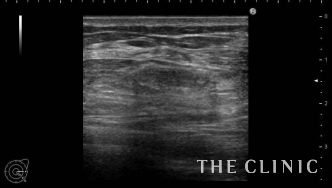

エコー検査では、両方のバストに多数のしこりを確認。超音波を反射しそれより内部が黒くなりなっていることから、しこりの辺縁には石灰化が認められます。

しこりはベイザーリポ(ベイザー脂肪吸引)の特殊な超音波で崩し、吸引針で穿刺することで除去しました。こちらの画像のように、エコーに映し出される映像を確認しながら行うことで、しこりに的確に吸引針を挿入することができます。